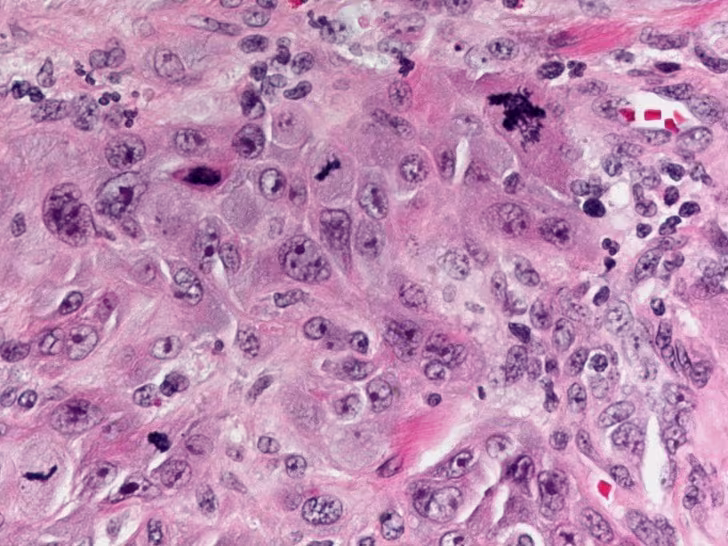

Histopathologic Findings The histologic sections of the incisional biopsy show infiltrating cords and islands of atypical squamous epithelium arising from dysplastic surface mucosa. There is a supporting fibrovascular connective tissue stroma with lymphocytic interface chronic inflammatory infiltrate. The epithelial cells displays pleomorphic round to oval nuclei with finely dispersed to vesicular chromatin, prominent nucleoli, increased nuclear to cytoplasmic ratio and pink focally dyskeratotic cytoplasm. There are numerous abnormal mitotic figures and focal single apoptotic cells.

Figure 4. High power histologic image showing atypical epithelial cells with pleomorphic round to oval nuclei, finely dispersed to vesicular chromatin, prominent nucleoli, increased nuclear to cytoplasmic ratio, and pink focally dyskeratotic cytoplasm. There are interspersed abnormal mitotic figures and single apoptotic cells.